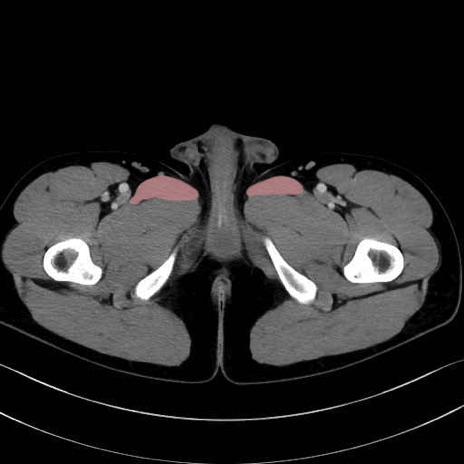

長内転筋(Adductor longus muscle)のCT画像の解剖

長内転筋 (Adductor longus)